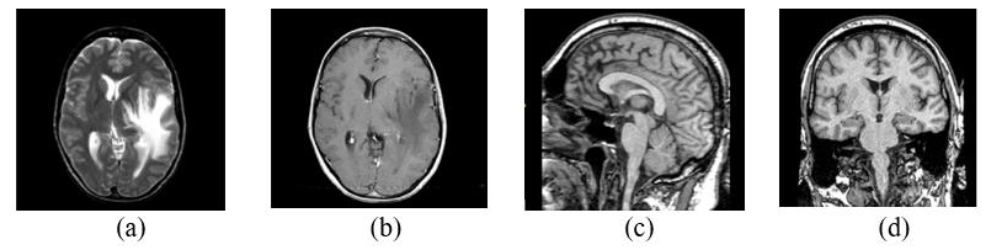

AANLIB was created as a dataset specific to assisting multimodal fusion and classification research for Alzheimer’s disease. It includes thousands of cases with T1-MRI, FLAIR, PET, and neurocognitive records. Unlike large datasets such as OASIS or ADNI, AANLIB provides images that are prepared for fusion (preprocessing corrects for skull stripping and registration). These standardized images significantly streamline the work in the MMIF workflows. The AANLIB’s corresponding images are archived in NIfTI format, and its accompanying ground truth labels are provided for employing it in supervised learning procedures. The open access for academic users makes it suitable for evaluating deep learning fusion algorithms [14]. The source images of the brain from AANLIB in axial, sagittal, and coronal sections are presented in Fig. (5).

AANLIB Source images of the brain in axial (a) and (b), sagittal (c), and coronal sections (d) [14].